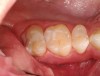

Fig 7. After properly etching the enamel and dentin, an adhesive bonding agent was applied to the preparation, which was then light-cured.

Figure 7

Fig 8. A flowable bulk-fill dentin replacement composite was placed deep into the preparation and adapted to the cavity walls.

Figure 8

Fig 9. View of the flowable bulk-fill dentin replacement increment before light-curing.

Figure 9